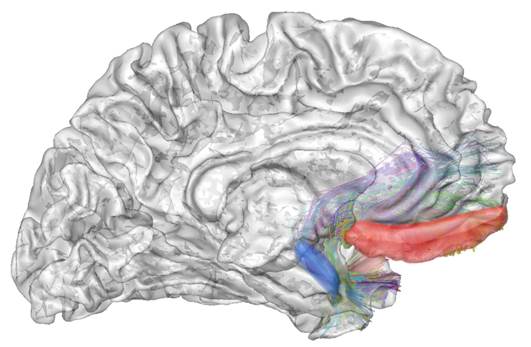

Photo : Réseau préfronto-amygdalien associé à la variation de SNAP25 visualisé en tractographie par IRM de diffusion. Crédit: Josselin Houenou /BrainVisa/Connectomist 2.0

Les résultats révèlent que la variation du gène SNAP25 change l’expression de la protéine associée dans le cerveau, ce qui impacterait le traitement de l’information entre les régions cérébrales impliquées dans la régulation des émotions. En lien avec ce mécanisme, l’étude d’imagerie génétique, combinant IRM anatomique et fonctionnelle de repos, montre que dans les deux cohortes, le variant à risque est associé à un plus grand volume d’une zone cérébrale, l’amygdale, et une connectivité fonctionnelle préfronto-limbique altérée.

Connexions fronto-limbiques associé à la variation de SNAP25 visualisé en tractographie par IRM de diffusion